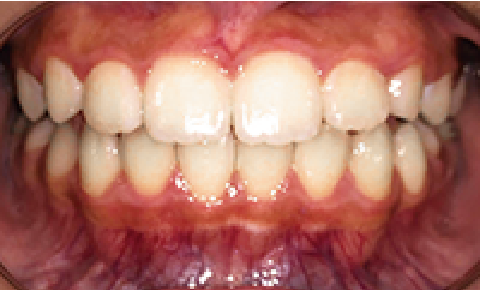

症例 : 39歳 男性

Before

After

主訴

空隙歯列(すきっ歯)

治療方法

インビザラインフル

総額治療費

790,000円(税込)

治療期間

6ヶ月

治療のリスク・副作用

矯正治療中は口腔内が少し狭く感じ、舌の動きにやや違和感が出る場合があります。

改善ポイント

できるだけマウスピースを長く装着していただくことで計画通りに治療をすすめることができます。マウスピース矯正は年齢制限がないため30.40代の方でも治療を行うことができ、また目立ちにくい装置のため、お仕事にも支障なく過ごしていただけました。